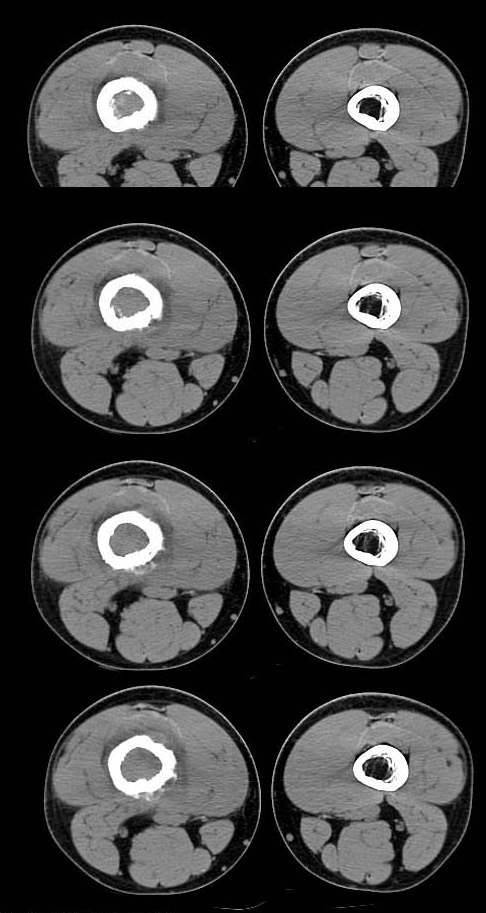

20岁,男,右股骨下端疼痛一个月,无发热,白细胞正常,皮肤不红,肿胀,触痛。

右股骨下端很长范围内的髓腔扩大,骨小梁破坏消失,皮质亦呈融骨性破坏,周围脂肪层次紊乱,肌肉受累及密度减低。考虑为:恶性骨肿瘤。请专家们分析骨肉瘤及尤文氏肉瘤的ct征象。

6.ct及mri:能较好地判断肿瘤的范围及侵犯软组织的情况。mri可见瘤体处广泛性骨质破坏,呈软组织肿块影;在t1加权像上呈均匀的长t1信号;在t2加权像上呈很长t2高信号。在ct上显示为源于骨组织的软组织肿块,骨质广泛破坏。

长骨ct见的较少,该病例股骨下端表现为边缘模糊的溶骨性破坏,伴有费用性脱钙,髓腔密度增高,呈毛玻璃样改变,病变周围软组织肿胀,脂肪间隙模糊,无骨膜反应,应密切结合临床,考虑骨纤维肉瘤或慢性骨脓肿。期待结果。

此病例基本可定是恶性骨肿瘤:髓腔内长范围肿块、皮质不规则破坏、软块及软组织浸润、瘤骨及不规则骨膜反应等。可以肯定地除外炎性病变和骨纤。

结合临床还是将尤文氏肉瘤放在前面,骨肉瘤不排除。纤维肉瘤及恶纤组多见老年人,不放在首要诊断范围内。